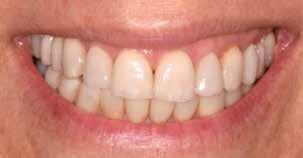

A fogszabályzó kezelések egyik legfontosabb célja, hogy elérjük a lehető legharmonikusabb interokkluzális fogérintkezéseket, továbbá az állcsont relációs helyzetének frontális és szaggitális síkban is megfelelőnek kell lennie. A fogszabályzás befejezésekor a fogpozícióknak nem orthodonciai, hanem protetikai szempontok szerint kell ideálisnak lenniük. Az Invisalign ClinCheck szoftver (Align Technology) segítségével a protetikus az orthodontussal együtt meg tudja határozni azokat a végső fogpozíciókat, amelyek a lehető legjobb végeredmény biztosításához elengedhetetlenek. Bizonyos klinikai paramétereket, mint a fogak klinikai koronájának nagyságát, az egyes fogak fogíven belüli optimális pozícióját, a fogívek egymáshoz viszonyított helyzetét, a fogak között látható rések nagyságát, a frontfogak tengelyének dőlését, az overjet és overbite mértékét már a kezelések megkezdése előtt pontosan definiálni kell. Ezeket az adatokat viszont csak a tervezett végleges fogpótlás ismeretében lehet meghatározni, ezért van szükség az orthodontus és a protetikus szoros együttműködésére.

A közös munka során az egyik legelső és legfontosabb feladat annak a meghatározása, hogy a páciens jelenlegi maximális interkuszpidációs helyzete (IKP) milyen mértékben tér el az

32 e-Journal DENTAL HÍREK

33 VII. ÉVFOLYAM – 2024. 3. SZÁM

1-4. ábra: Kiindulási állapot. 5. ábra: ClinCheck szoftverrel történő kiértékelés. A kiindulási és az orthodonciai kezelés végén elérni kívánt állapot összehasonlítása. 6-9. ábra: Az orthodonciai kezelés végén elért állapot.

10. a-c. ábra: Módosult passzív erupció jelenlétének diagnosztizálása radiológiai felvételek segítségével (altered eruption radiographic technique; AlteRx).

11. a-b. ábra: A gingivectomia és frenulectomia elvégzését követően látható állapot.

12. a-d. ábra: Az állcsont relációs helyzetét a helyreállítás befejezése után elérni kívánt állapotot bemutató mock-up felhelyezését követően rögzítettük az arcív és a harapási sánc segítségével.

állcsontok centrális relációs helyzetétől (CR). Ezt a helyzetet úgy is leírhatnánk, mint az a legideálisabb állkapocs-ízületi helyzet, amely elérését követően a lehető legkedvezőbb állkapocshelyzetből történhet meg az alsó és felső fogív végleges fogpótlásokkal történő helyreállítása. Ennek a meghatározásakor a frontális és a szaggitális síkban megfigyelhető komponenseket is figyelembe kell venni. Az optimális állcsont relációs helyzetének megállapítása előtt elengedhetetlen az állkapocs-ízület beprogramozása, a rágóizmok lazítása, és

állkapocs-ízületi rendellenességek fennállásának ellenőrzése. Amennyiben állkapocs-ízületi rendellenességeket diagnosztizálunk, úgy először gnatológiai terápiát alkalmazunk, melynek célja a rágóizmok működésének és az állkapocs-ízület egészségének helyreállítása. A komplex rehabilitációs beavatkozások kivitelezésének megtervezését csupán az új, biológiai és funkcionális szempontokból ideális állkapocs-ízületi helyzet elérését követően szabad megkezdeni.

34 e-Journal DENTAL HÍREK